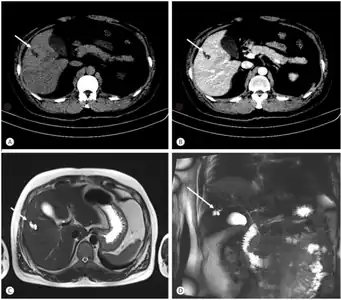

Bileduct dilatation in segment 5 arrow a,b) CT, c) MRI, d) MRCP -

Magnetic resonance cholangiopancreatography (MRCP) of Caroli disease, showing cystic dilatations of bile ducts.[1]